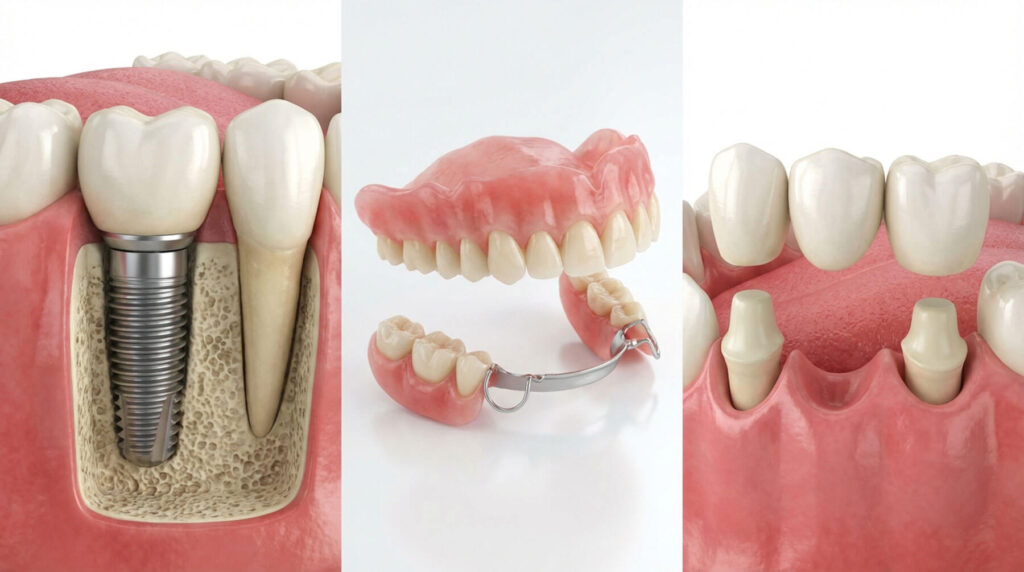

Dental implants are a widely used option for tooth replacement. They use a titanium post placed in the jawbone to support a crown or restoration. As a result, many patients choose implants for their stability and natural feel.

Once the post fuses with bone, your dentist places a custom crown or restoration designed to match your smile.

Dentures are removable prosthetic devices that replace missing teeth. They come as complete dentures (all teeth) or partial dentures (some teeth). Therefore, dentures can be a practical option when you want an affordable, removable solution.

Dental bridges replace one or more adjacent missing teeth by anchoring to neighboring teeth. A dentist creates a customized bridge and secures it to the natural teeth on either side of the gap. As a result, you restore function and improve the look of your smile.

Endosteal implants are the most common type. Dentists place the post directly into the jawbone, and many patients qualify for this approach.

Subperiosteal implants sit on top of the jawbone under gum tissue. In some cases, dentists consider them when bone height is limited.